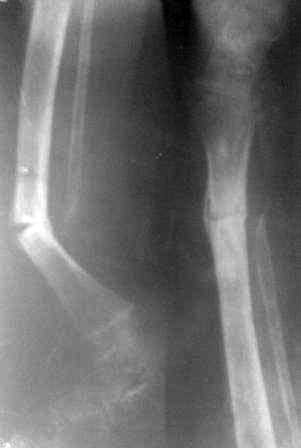

Уважаемые коллеги.Очень прощу помочь в одном сложном деле. Девочка 2005г.р. В середине 2008 г падает с велосипеда с дедом, возможно был перелом н/з костей левой голени, лечение у знахаря-табиба, но ребенок не смог бегать, часто падал, начал хромать. Май 2009г. обратились к нам, установлен д-з « вялоконсолидирующаяся перелом н/з б/берцовой кости, несросшийся перелом м/берцовой кости со смещением по ширине». Мы решили гипсовая повязка и ходьба с нагрузкой, но по категорическому требованию родителей исправить деформацию м/берцовой кости, произвели операцию ( на свою голову )»о/ репозиция и и/м фиксация спицами м/берцовой кости». Теперь началась самая интересная история! Ч-з недели две в обл. п/о раны м/берцовой открылась свищ с кровянистым выделением, гноя не было, на р-грамме лизис концов отломков м/берцовой кости, к-рый начал прогрессировать, консультирована онкологами, цитология, с подозрением направлена в центральные институты, сделана КТ, онкологическое исключили, в августе попали в остеомиелитический центр, где произведена резекция м/б на протяжение 6-7см, все зажило и выписали (снимок-1). 2010г в мае повторно получила травму, наложена гипсовая повязка (снимок-2) и через 1-2 месяца в одном из центральном институте произведена КДО аппаратом Илизарова , который снят ч-з три месяца (снимок-3) и долго ходила на костылях-мать заставила, как начала наступать, появилась деформация, заказали ортез и так ходила, но деформация прогрессировала, Обратилась к нам в апреле 2012г,(снимок-4) произведена постепенная коррекция на аппарате, и замена на БИОС 01.03.12г плечевым гвоздем, ЭОП нет, поэтому осталась несколько антекурвация (снимок-5), ребенок ч-з неделю начала ходить.Повторный осмотр 22.06.12г- деформация усиливается, за три месяца сращение очень слабое.(снимок-6). (Жаль что многие р-снимки не сохранились, мать обещала хотя бы часть найти)!Что теперь делать? Удалить дистальные винты и пробовать исправить на аппарате, или гвоздь убрать , коррекция на аппарате и после рассверливания повторный БИОС? Уважаемые коллеги, какие варианты предлагаете? С уважением Абдурашид.